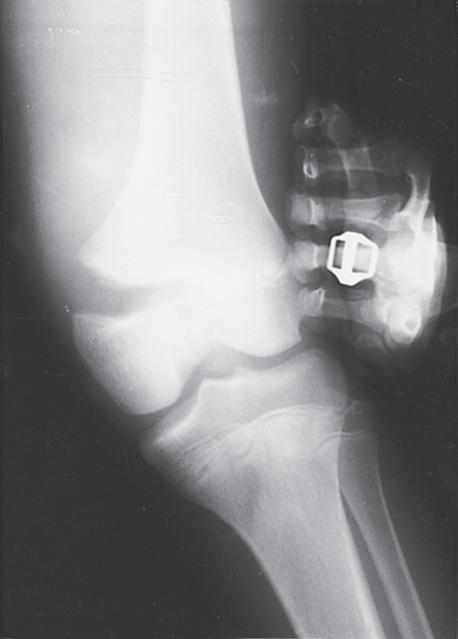

ANATOMIC DIFFERENCES OF PEDIATRIC BONES

As the skeleton of a child grows, it develops from a relatively elastic and rubbery type of biomechanical material to the more rigid structure of an adult skeleton. Because of the amount of radiolucent cartilaginous material in pediatric bone, comparison films are sometimes necessary to determine whether a radiograph is abnormal, and this lack of clarity in the radiograph can make diagnosis of fractures difficult. The types of injuries may also be different in children; for example, ligamentous injuries and dislocations are rare. Injuries around the knee frequently lead to ligamentous and meniscal injuries in adults. In children, the distal femoral or proximal tibial physis is more likely to be injured because it is the weak link (Fig. 1.7). Previously, stress radiographs were recommended, but these are usually unnecessary because the diagnosis can be made by a complete history and physical examination and confirmed at follow-up when radiographs demonstrate a widened physis consistent with a healing growth plate injury. Ligamentous injuries in skeletally immature children are uncommon, but they do occur and become more frequent in adolescence as

the transition to skeletal maturity occurs.5 As noted earlier, traditional teaching that twisting ankle injuries cause distal fibular physeal injuries more commonly than ligamentous injuries in children has been challenged by studies using advanced imaging techniques.4,5